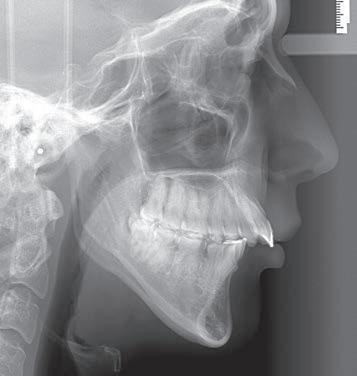

Figs. 1a–h: Initial situation: patient’s facial view (a-c); intraoral view (d-f); cephalometric X-ray (g); pantomograph X-ray (h).

A female, age 23 years, 5 months, presented for treatment exhibiting a moderate Class III malocclusion with negative overjet, proclined lower lip with flat supramentale sulcus, open bite and crowding in the lower arch. The treatment plan was to distalise the lower dentition into a Class I occlusion (Sagittal First) using the Carriere Motion CL III Appliance, then generate space to alleviate the lower arch crowding and close the bite, utilising light-force archwires in a passive, self-ligating system. While tongue trainers would be bonded in conjunction with the fixed appliances later in treatment, the patient would also engage in tongue training exercises to correct her improper

A 27-year-old female patient presented for treatment exhibiting a Class II, division 1 malocclusion with a severely protrusive maxilla and a severely retrusive mandible. The patient had had previous orthodontic treatment with extraction of the lower premolars. In consultation with other orthodontists, orthognathic surgery was recommended, which she wanted to avoid.

The treatment plan was to reposition the mandible forward, placing the case into a Class I occlusion (Sagittal First) using the Carriere Motion Clear Class II Appliance, then complete treatment utilising light-force archwires in a passive, self-ligating system. The Motion Clear Appliance is the latest addition to the family of Motion appliances, designed for the patient with high aesthetic demands.